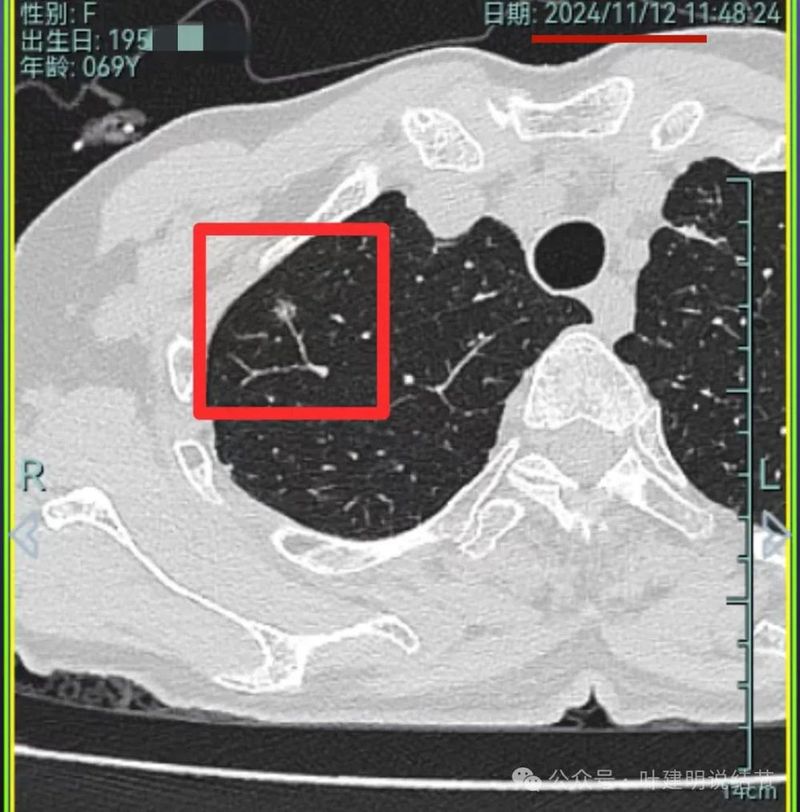

再看2024年11月复查的情况:

病灶1仍磨玻璃稍高密度,有血管进入,大小无显著进展,但密度从开始到现在是有所进展的。

病灶2与5年前比也说不上明显进展。

病灶3仍是混合密度,伴有收缩力,但实性部分并无聚拢性,也不是密度很高的样子。

我想我们这样也来考虑问题:1、左侧已经手术的确诊是肿瘤性质,左上已经消融的也是随访持续存在的磨玻璃密度结节,虽然没有病理依据,仍然要考虑广义上来讲的肿瘤范畴,看了以前的片子,从2019年到2023年并没有显著的进展,大概是肺泡上皮不典型增生可能性大。右侧的也有磨玻璃结节与混合磨玻璃结节考虑是肿瘤范畴的。所以总体上两肺多原发早期以磨玻璃为表现的肺癌,整体风险都不大。2019年切除的左肺下叶病灶也是纯磨玻璃密度,其实如果继续随访或者只做楔形切除也并没有什么关系。这说明体质本身或者致病的因素,就是容易长磨玻璃肺癌的,即便把目前发现的都解决,后续仍可能再有新的。原因不明,致病因素仍在。2、右肺上叶红色之处从2019年开始,是逐渐进展的,当然即便是现在,也不是说危险就已经很大,考虑仍然是原位癌或者微浸润性腺癌可能性大;中叶蓝色这处乍一看像至少是微浸润,但前后对比以后发现从2019年到现在,几乎没有显著进展,这样的话慢性炎伴肺泡上皮增生或者伴纤维增生也是有可能的,至少风险并不能认为大;右肺下叶黄色这一处,使纯磨玻璃密度,整体轮廓与边界清楚,考虑是肿瘤范畴的,不典型增生可能性较大,也有可能原位癌,随访稍有进展,风险仍然不大;中叶绿色这处是慢性炎伴钙化的,靠近叶裂的地方也像慢性炎,但此处随访有所进展。不过因为有卫星灶,整体显得比较散,所以虽然恶性可能性较大,但也不能完全除外炎性的可能性。当然如果此灶确实恶性,那风险则相对较其他进展缓慢的要高一些。从目前右侧所在的这些病灶来讲,真正有一定的风险而且最为确切的是红色这处,而且应该也没有到浸润性腺癌或者说不处理会要转移很危险这种程度。3、明确了多原发早期肺癌没有办法预防与控制,也明白了目前已经存在的较明显的这些病灶总体风险的高低。我们再来考虑需不需要近期干预处理。左侧既手术过又消融过,右侧的多发病灶目前又还没有到危险很高的程度,又没有办法预防后续再有新的病灶。我个人偏保守,我觉得仍然可以半年复查随访,如果最具风险的病灶有进展并且不处理可能导致不良后果,到这样的程度再来考虑综合如何处理干预便可。4、假如右侧我们予以处理,上叶红色的以及中叶蓝色的都可以楔切,但绿色考虑良性的再进展或以后像恶性时怎么办?而若中叶切除加上叶楔切,在左侧已经手术过的情况下肺功能影响相对也不小,何况右下比较中间的位置还有桔色这处呢。当然右下这处得考虑消融。所以,我的想法还是能熬再熬下,待其他监测有变化再通盘考虑。意见供参考!